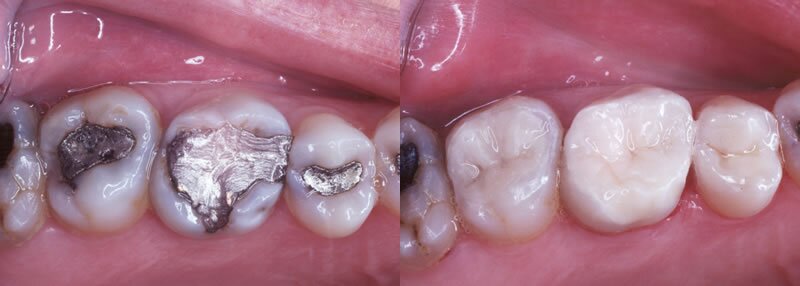

Inlays and onlays are large porcelain fillings used when the decay on a tooth is between 1/3 and 5/6 of the tooth. Inlays and onlays are pre-formed porcelain pieces that have been shaped to a mould of the tooth’s original surface and the new surface of the cleaned out tooth. This piece is then cemented to the clean tooth to restore it to its properly functioning shape and size. Dental inlays and onlays are among many other dental procedures that restore your tooth back to its original shape, size and function. Our doctors have extensive experience in determining the most fitting restorative procedure for your case upon your dental assessment. We will discuss the procedure with you in detail and make sure that you feel comfortable and relaxed before, during and after the treatment.

Inlays